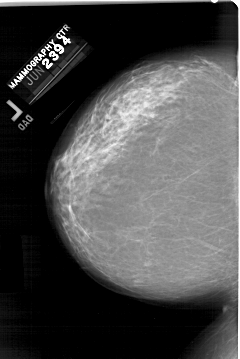

A_1330_1.LEFT_CC

LEFT_CC LINES 6451 PIXELS_PER_LINE 4306 BITS_PER_PIXEL 12 RESOLUTION 43.5 NON_OVERLAY